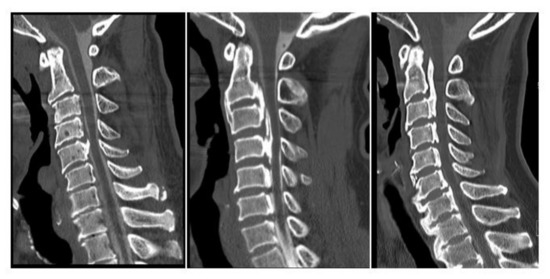

2.3. Radiologic Evaluations